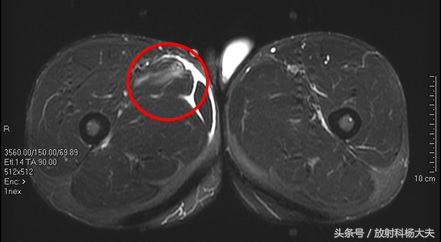

肌肉拉伤可能是足球场上最多见的损伤了,为啥有的拉伤冷敷,休息就能好,而有的拉伤得做手术,甚至有可能导致职业生涯终止?其实答案都在MRI上,用MRI看肌肉有无拉伤,拉伤的程度如何,是目前最好的选择。

在MRI上,少于5%肌肉纤维的断裂,为I级损伤,大于5%,但没完全断裂的为II级损伤;完全断裂则为III级。比较多见的是I级损伤,MRI上可以看到肌肉的轮廓存在,但能看到白白的一片,代表水肿。